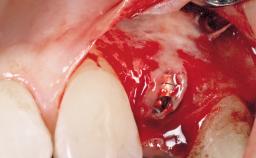

A 30-year-old female patient had lost tooth 21 and was referred to our clinic for consultation and treatment. Due to advanced apical infection, tooth 21 had been extracted two months earlier at another clinic and an acrylic-resin tooth had been bonded to the adjacent teeth. The patient desired implant treatment to avoid any damage to the adjacent natural teeth. While the patient had no history of any systemic disorder, she was a heavy smoker and exhibited medium to advanced periodontitis in the entire jaw. After the initial treatment to achieve a pocket probing depth of less than 4 mm and no bleeding on probing, a decrease in the height of the papillae mesial and distal to the extraction site and overall gingival recession were observed.